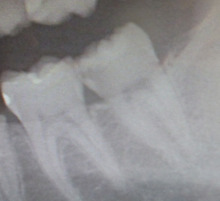

レントゲンを撮影しました。

赤い丸印内に 黒い影が見えます。

これが もし虫歯です。

レントゲンを撮らなければ 絶対に 見逃します。

レントゲンを使用した、定期健診 が大事ですね!!